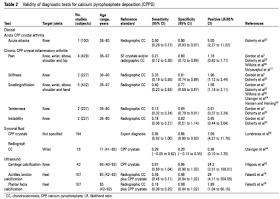

- CPPDに関する検査の特性について

- CPPDリスク因子

- ルーチン検査とできるように、それぞれの画像検査のvalidation